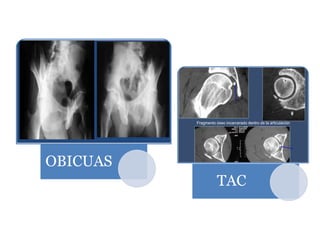

Rx

anteroposterior

de pelvis

Lateral de

cadera

afectada

TAC

Evaluar la presencia de

posible fragmentos

intraarticulares

La congruencia de la

cabeza femoral

Descartar fracturas

asociadas a la cabeza

del fémur y acetábulo

OBICUAS